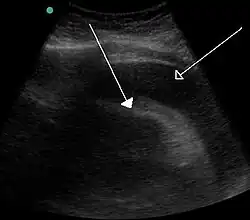

A large anechoic (black) pericardial effusion as seen on ultrasound. Closed arrow: the heart, open arrow: the effusion -

Echocardiogram (ultrasound): when pericardial effusion is suspected, echocardiography usually confirms the diagnosis and allows assessment of the size, location and signs of hemodynamic instability.[4] A transthoracic echocardiogram (TTE) is usually sufficient to evaluate pericardial effusion and it may also help distinguish pericardial effusion from pleural effusion and MI. Most pericardial effusions appear as an anechoic area (black or without an echo) between the visceral and the parietal membrane.[1] Complex or malignant effusions are more heterogeneous in appearance, meaning they may have variations in echo on ultrasound.[5] TTE can also differentiate pericardial effusion based on the size. Although it's difficult to define size classifications because they vary with institutions, most commonly they are as follows: small <10, moderate 10–20, large >20.[5] An echocardiogram is urgently needed for evaluation when there is concern for hemodynamic compromise, a rapidly developing effusion or history of recent cardiac surgery/procedures.[1]